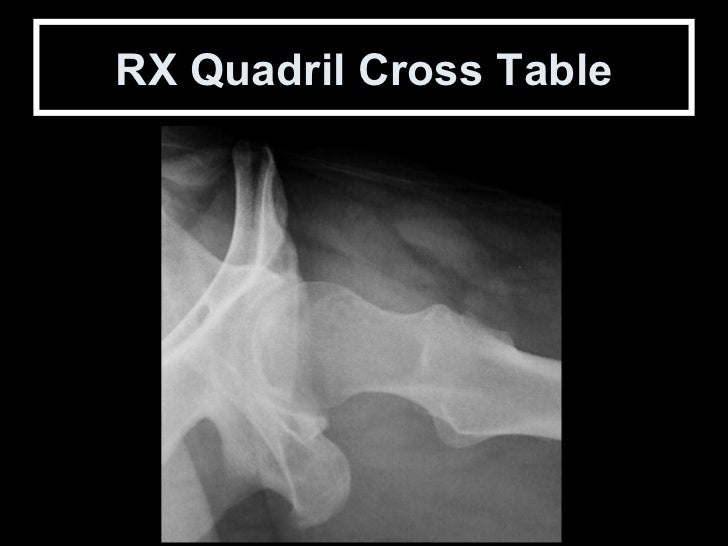

Cross Table (Arcelin) Método de Danelius Miller: Incidência Axio-lateral infero-superior.

Posicionamento Perfil Cirúrgico de Arcelin  ( Cross Table) Posição  supina com flexão do quadril contralateral e raio hori...

Cross Table ou Arcelin Assim como na incidência de Ducroquet, o colo femoral é visto em perfil permitindo uma boa avaliaçã...

RX Quadril Cross Table